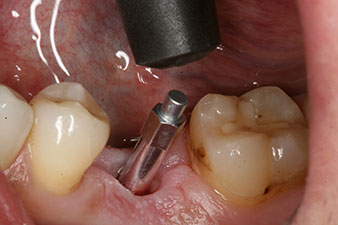

Implantat

Figura 3: Después de realizar la preparación con el motor de implantes Implantmed, se enroscó mecánicamente un implante (diámetro 4 mm, longitud 12 mm) con un torque de 43 Ncm.

Tras la extirpación minuciosa del tejido de granulación, se incorporó el implante tal como se había planificado (blueSky, bredent).

SmartPeg

Figura 4: Poste de medición atornillado SmartPeg para determinar el cociente de estabilidad del implante con el módulo Osstell ISQ de W&H.

El torque en el momento de la carga mecánica fue de 43 Ncm. Asimismo, después de atornillar un poste de medición especial adaptado al sistema de implante (SmartPeg), el valor ISQ se determinó con la sonda del módulo Osstell ISQ de W&H.